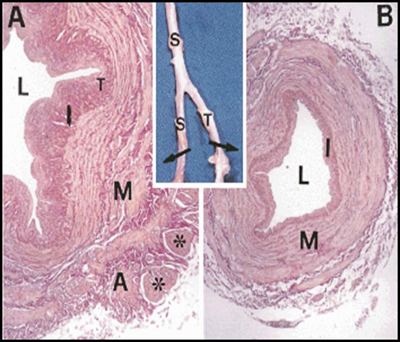

Διατομή φλεβιδίου σε ηλεκτρονικό μικροσκόπιο (εικόνα 2). Διακρίνονται η βασική

μεμβράνη, το κυτταρόπλασμα των ενδοθηλιακών κυττάρων και τα περικύτταρα.

Σε αντίθεση με τις αρτηρίες, το τοίχωμα των περισσότερων φλεβών δεν αποτελείται

από 3 ευδιάκριτους χιτώνες, είναι λεπτότερο, σαφώς φτωχότερο σε ελαστικές και

λείες μυικές ίνες και διατείνεται εύκολα, ανάλογα με την ποσότητα του περιεχομένου

αίματος.